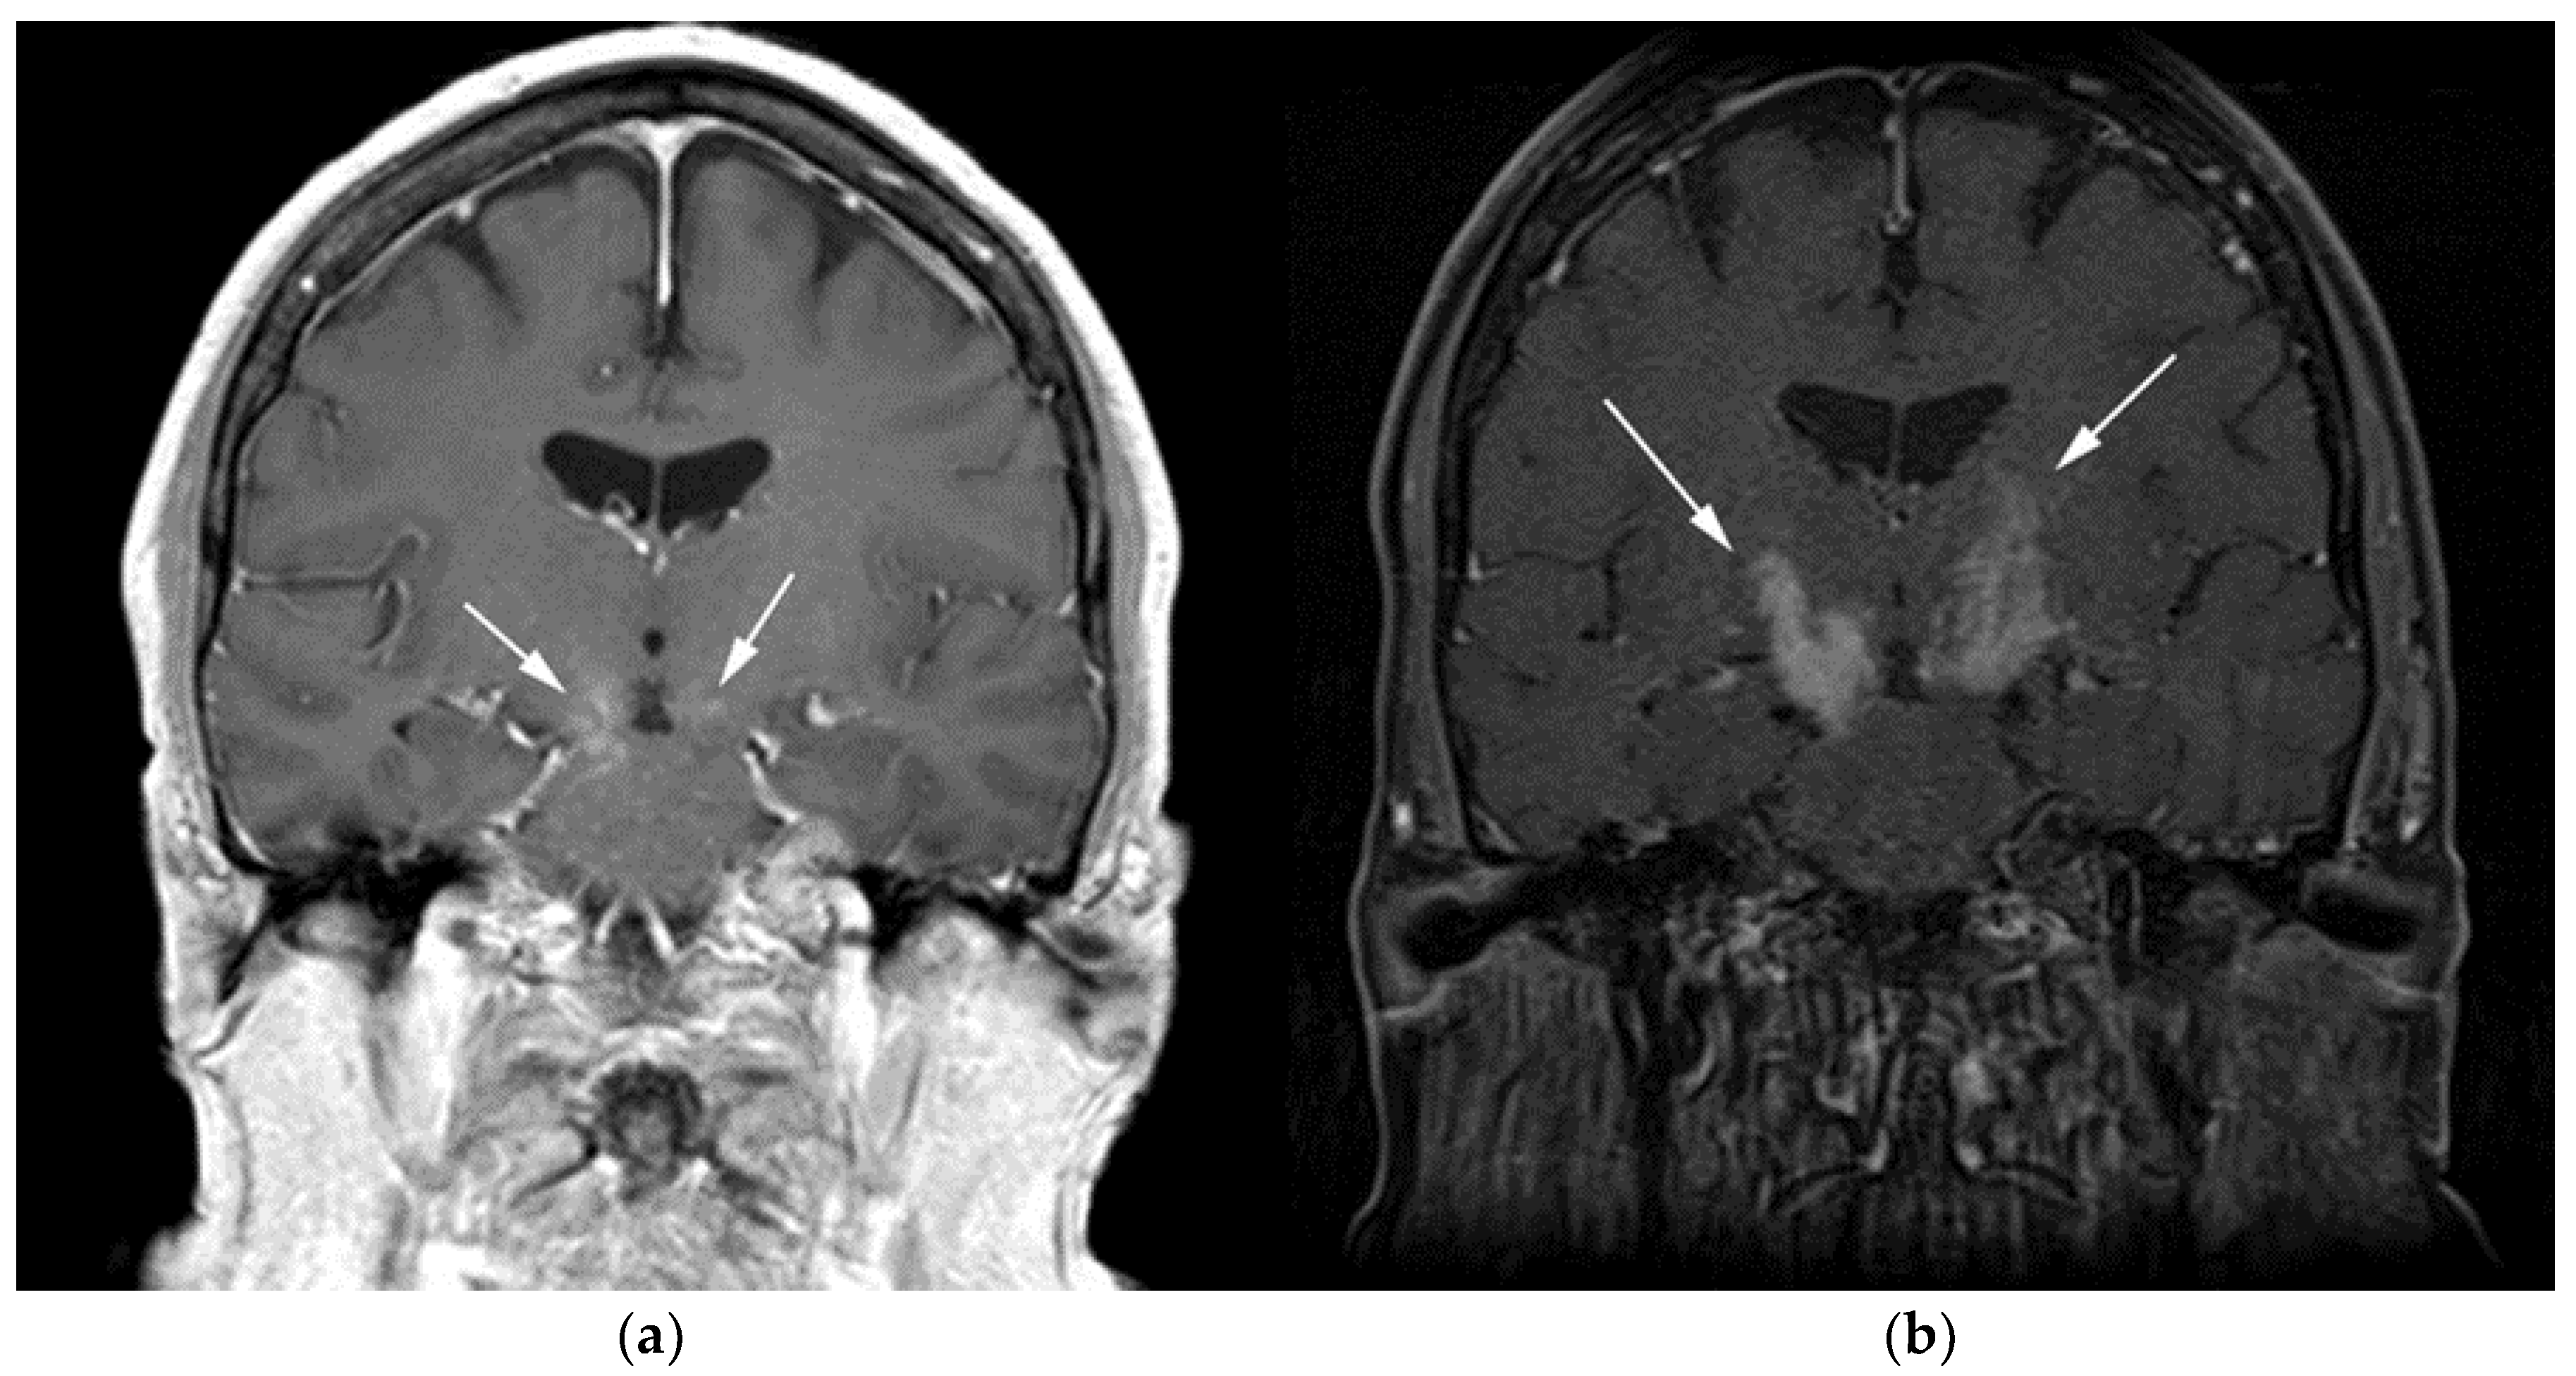

WM patients can also present with splenomegaly with or without focal lesions and lymphadenopathy typically within the axillary, retroperitoneal, and/or inguinal nodal stations (Figure 12). Cranial nerve deficits can be a manifestation of Bing–Neel syndrome, a rare CNS manifestation seen in WM disease [45,48,52,54]. In Bing–Neel syndrome, neurological symptoms can be directly related to infiltration by lymphoplasmacytic cells or indirectly result from the deposition of circulating IgM immunoglobulin on the brain parenchyma, spinal cord, or cranial or peripheral nerves (Figure 13). Additionally, 18F-FDG PET/CT plays an important role in monitoring therapeutic response after treatment initiation, especially with rituximab. WM patients tend to show elevated IgM levels, known as an IgM flare, which may mimic progressive disease. Imaging plays a pivotal role to differentiate between an IgM flare and true progression, thus obviating the need for repeated marrow biopsy [52]. Imaging may also help in excluding the development of myelodysplastic syndromes, acute leukemia, or DLBCL transformation [52].

Figure 13.

Patient with known diagnosis of lymphoplasmacytic lymphoma (LPL). (a) Coronal T1 post-contrast of the brain image shows diffuse leptomeningeal enhancement (black arrows). (b) Axial MRI T1 post-contrast image of the lumbosarcal spine in the same patient shows diffuse epidural soft tissue thickening and enhancement of the cauda equina nerve roots (white arrows). (c) Microscopic examination of the lymph node shows effaced architecture by infiltrative diffuse sheets of atypical lymphoid cells with plasmacytoid morphology. Tumor cells are positive for CD20 and are monotypic, expressing kappa or lambda light chains. (Original magnification 400×, H&E stain). CNS involvement in is an extremely rare variant known as Bing–Neel syndrome (BNS).